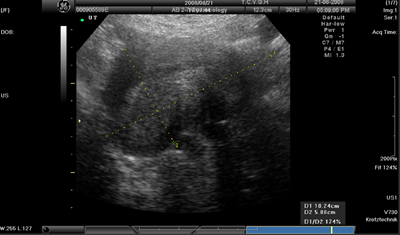

Her ultrasound exanimation performed at 2013 July 31 revealed the size of the uterus as 94.9 × 65.0 × 69.9mm. The ultrasound graph is shown in Figure 3. The value of serum CA-125 level, menstrual bleeding and menstrual pain are shown in Figure 2.